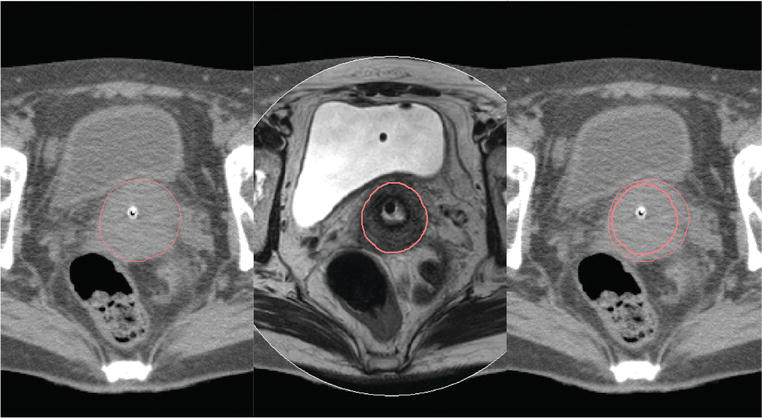

Điều trị ung thư cổ tử cung chính xác hơn bằng phương pháp xạ trị gần dưới chụp CT và MRI, vì phương pháp này nhắm vào khối u trong khi vẫn bảo vệ được mô khỏe mạnh.